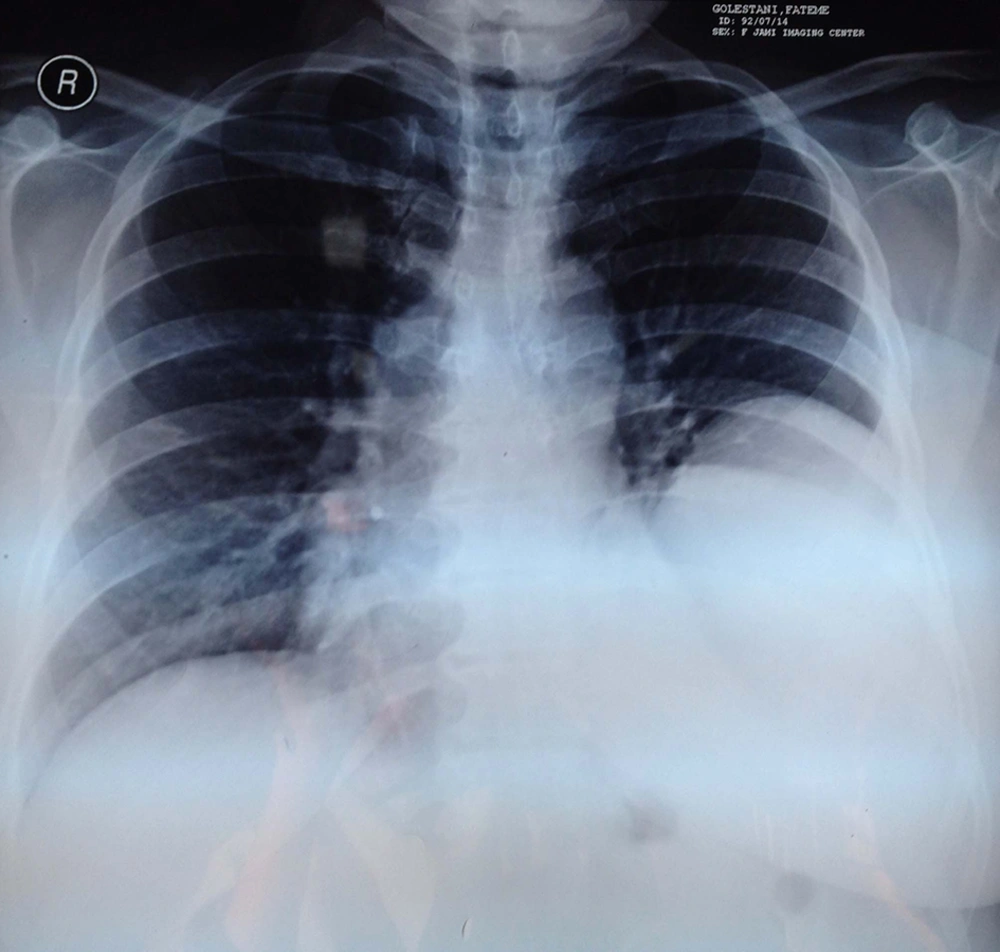

In trans-thoracic echocardiography, cardiac ejection fraction (EF) was reported about 55% with normal left and right ventricular size and function; however, a large cystic mass in postrolateral of pericardium was also noted. The chest radiography revealed a mass lesion with a homogenous shadow in the left lung (Figure 3).